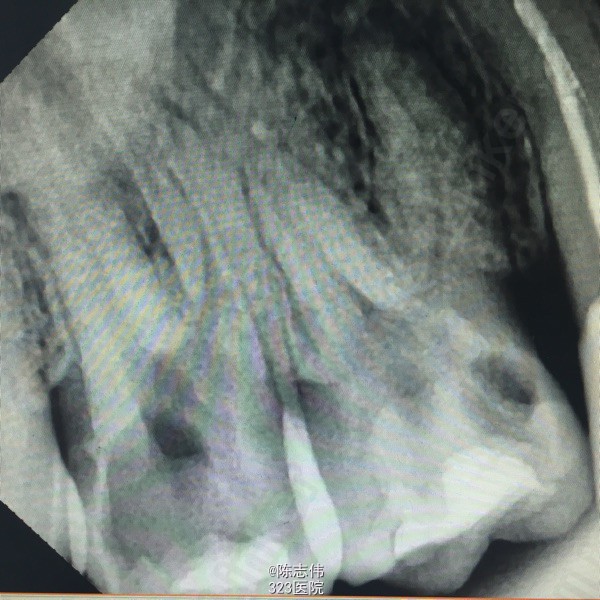

16近中颊部龋损,探深及龈下1mm,颌面白色充填物,冷(+) 松动(-) 叩(-)

17颊侧大面积龋损,缺损及龈下2mm,探(++) 叩(+) 冷(++) 松动(-)

x线示:16龋损近髓

17,45缺损及髓,根尖无明显异常